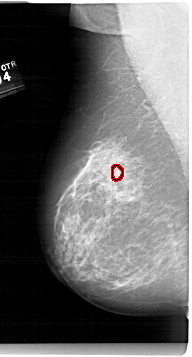

A_1679_1.RIGHT_CC

RIGHT_CC LINES 6256 PIXELS_PER_LINE 3331 BITS_PER_PIXEL 12 RESOLUTION 43.5 NON_OVERLAY

FILE: A_1679_1.LEFT_CC.OVERLAY

TOTAL_ABNORMALITIES 1

ABNORMALITY 1

LESION_TYPE MASS SHAPE LOBULATED MARGINS OBSCURED-CIRCUMSCRIBED

ASSESSMENT 4

SUBTLETY 3

PATHOLOGY BENIGN

TOTAL_OUTLINES 1

BOUNDARY